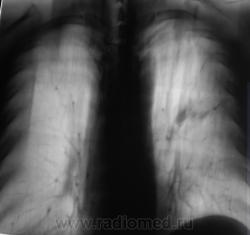

При расшифровке флюорограмм пациент "взят на контроль". Жалоб пациент не предъявляет. Подняли "архив", флюорограмма за 2009 г. - "норма".

Произвели стандартное дообследование.

Томограммы.